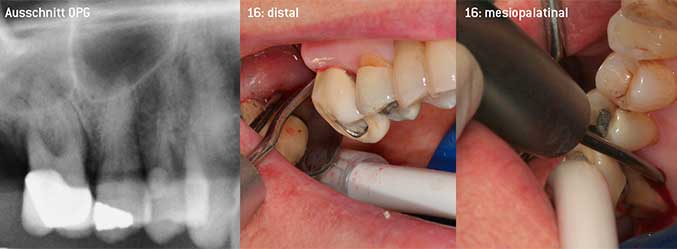

Als Initiatoren zur Entwicklung der neuen diamantierten Luftscaler-Spitze 3AP sahen es beide Zahnärzte als notwendig an, die Einschränkung in der Handhabung bisher kommerziell vermarkteter diamantierter Spitzen insbesondere während der Furkationstherapie oder in engen Knochentaschen zu verbessern. Dies sollte unabhängig von nicht-chirurgischem (Abbildung 2) oder chirurgischem Vorgehen sein (Abbildung 3).

Das Ziel bestand darin, eine universell einsetzbare Spitze zu entwickeln, um zeitraubende Spitzenwechsel zu vermeiden. Daneben sollte aber die Anwendung der neuen Arbeitsspitzen sowohl in engen Knochentaschen von distal als auch am distalen Furkationseingang von Oberkiefermolaren einfacher sein und infolgedessen eine effektivere Instrumentierung ermöglichen. Dies wurde durch einen größeren Durchmesser des Instrumentenbogens (Abbildung 1) erreicht, was gerade bei Zähnen mit fortgeschrittenem Attachmentverlust und Furkationsbeteiligung von großem Vorteil während des geschlossenen Debridements ist (Abbildung 4).